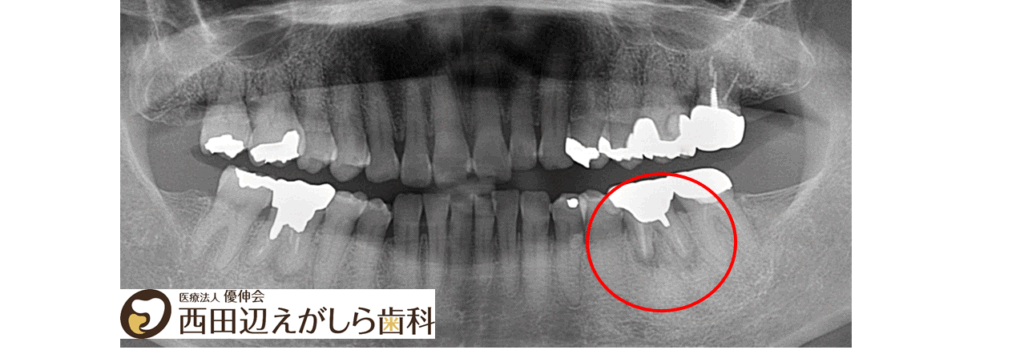

初診時にレントゲン検査を行ったところ、左下6番の歯の根の先に感染が広がっており、根尖病巣が認められました。これが、繰り返す腫れや、噛んだときの痛みの原因になっていると考えられました。

さらに詳しく確認すると、病巣は比較的大きく、歯根も短くなっており、歯にヒビが入っている可能性も否定できない状態でした。そのため、保存は難しいと判断し、抜歯が必要であることをご説明しました。